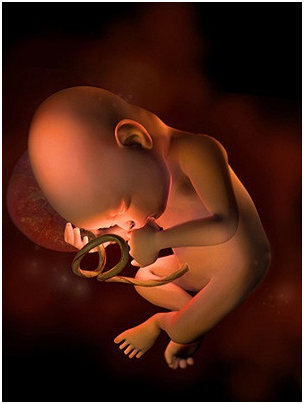

怀孕第12周现在胎儿身体的雏形已经发育完成了,你的脸和脖子上可能会不同程度地出现黄褐斑,腹部...

怀孕第12周现在胎儿身体的雏形已经发育完成了,你的脸和脖子上可能会不同程度地出现黄褐斑,腹部... -